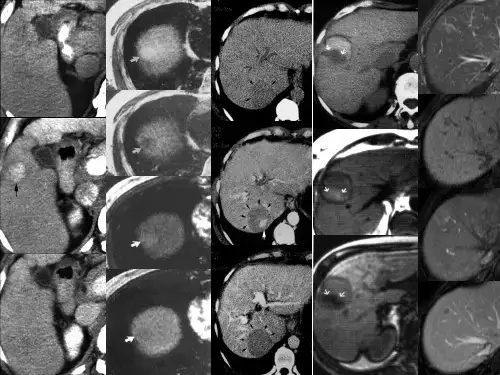

肝硬化结节的影像诊断PPT学习课件